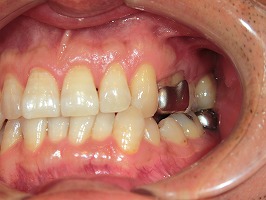

F様のケースです。笑うと光る左上の銀歯が気になるとのことでしたので、ジルコニアの被せ物に取り替える治療を行いました。

【術前】